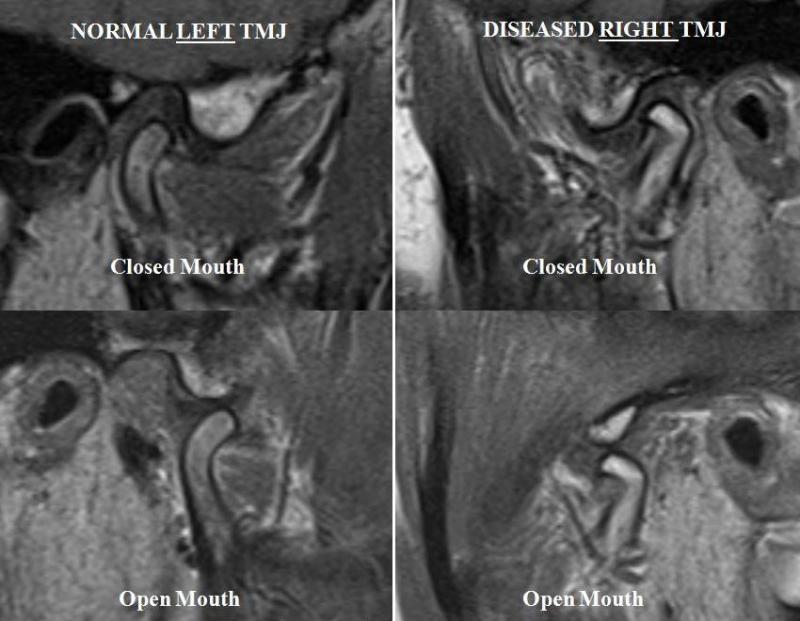

Diagnosis and treatment of temporo-mandibular joint (TMJ) disorders including Arthrocentesis, Arthroscopic Surgery (See Images Below) and open joint surgery of the TMJ including total joint replacement (TJR)

Arthroscopy of the temporomandibular joint (TMJ) is a minimally invasive surgical method of diagnosing and treating TMJ dysfunctions, in cases where nonsurgical treatment has failed to yield beneficial results. Findings obtained from diagnostic arthroscopy have yielded a new appreciation for the diagnosis of TMJ pathology, while arthroscopic operative procedures have been developed that replace open surgery for many pathological conditions. The goal of such arthroscopic surgical intervention is to restore functional range of motion, without pain or limitation, and an improved sense of well-being over time. As in all other joint surgeries, TMJ arthroscopy requires a high degree of technical skill and expert patient management for optimum success which we provide at our hospital.

Our clinic provides both non-surgical and surgical treatment modalities of the TMJ. The OnPoint™ 1.2 mm Scope System is an innovative breakthrough that provides minimally invasive visualization of the TMJ in the comfort and convenience of an office-based setting.

This scope is basically a new device that utilises rigid fibre-optic technology to visualize the superior and inferior spaces of the TMJ in a clinic and operating theatre settings under local anaesthesia and intravenous sedation or general anaesthesia. Since it comes in a 1.2mm (18 gauge needle) Scope System it is designed to provide minimally invasive diagnostic and operative procedures.